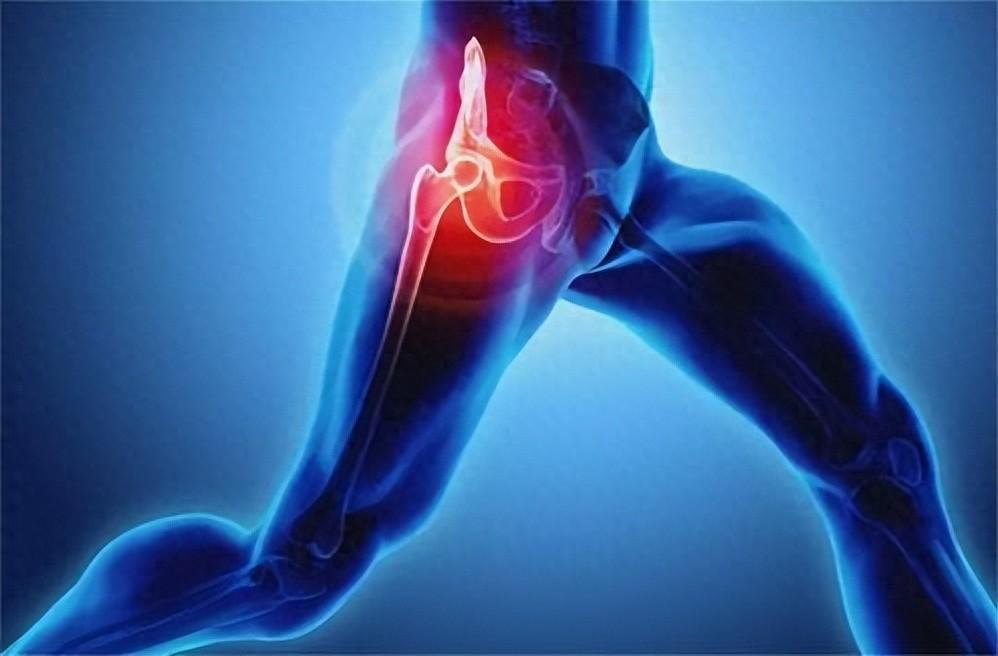

4、不對稱磨損:長短腿

有些人髖關節有問題,走路會以屁股帶腿,拖著腿走路。由於常常拖腳走,會磨損鞋後跟,甚至導致左右腳鞋底磨損不同。

此外,也可能是雙腳長度不等所致。長短腳的成因除先天性外,還可能是骨盆傾斜、甚至髖關節半脫位。此外,雙腿長度不同,走路動作也不一樣,左右腳的鞋底磨損程度通常也不同,長腿那隻腳鞋底磨損小,短腿那隻腳鞋底磨損大。